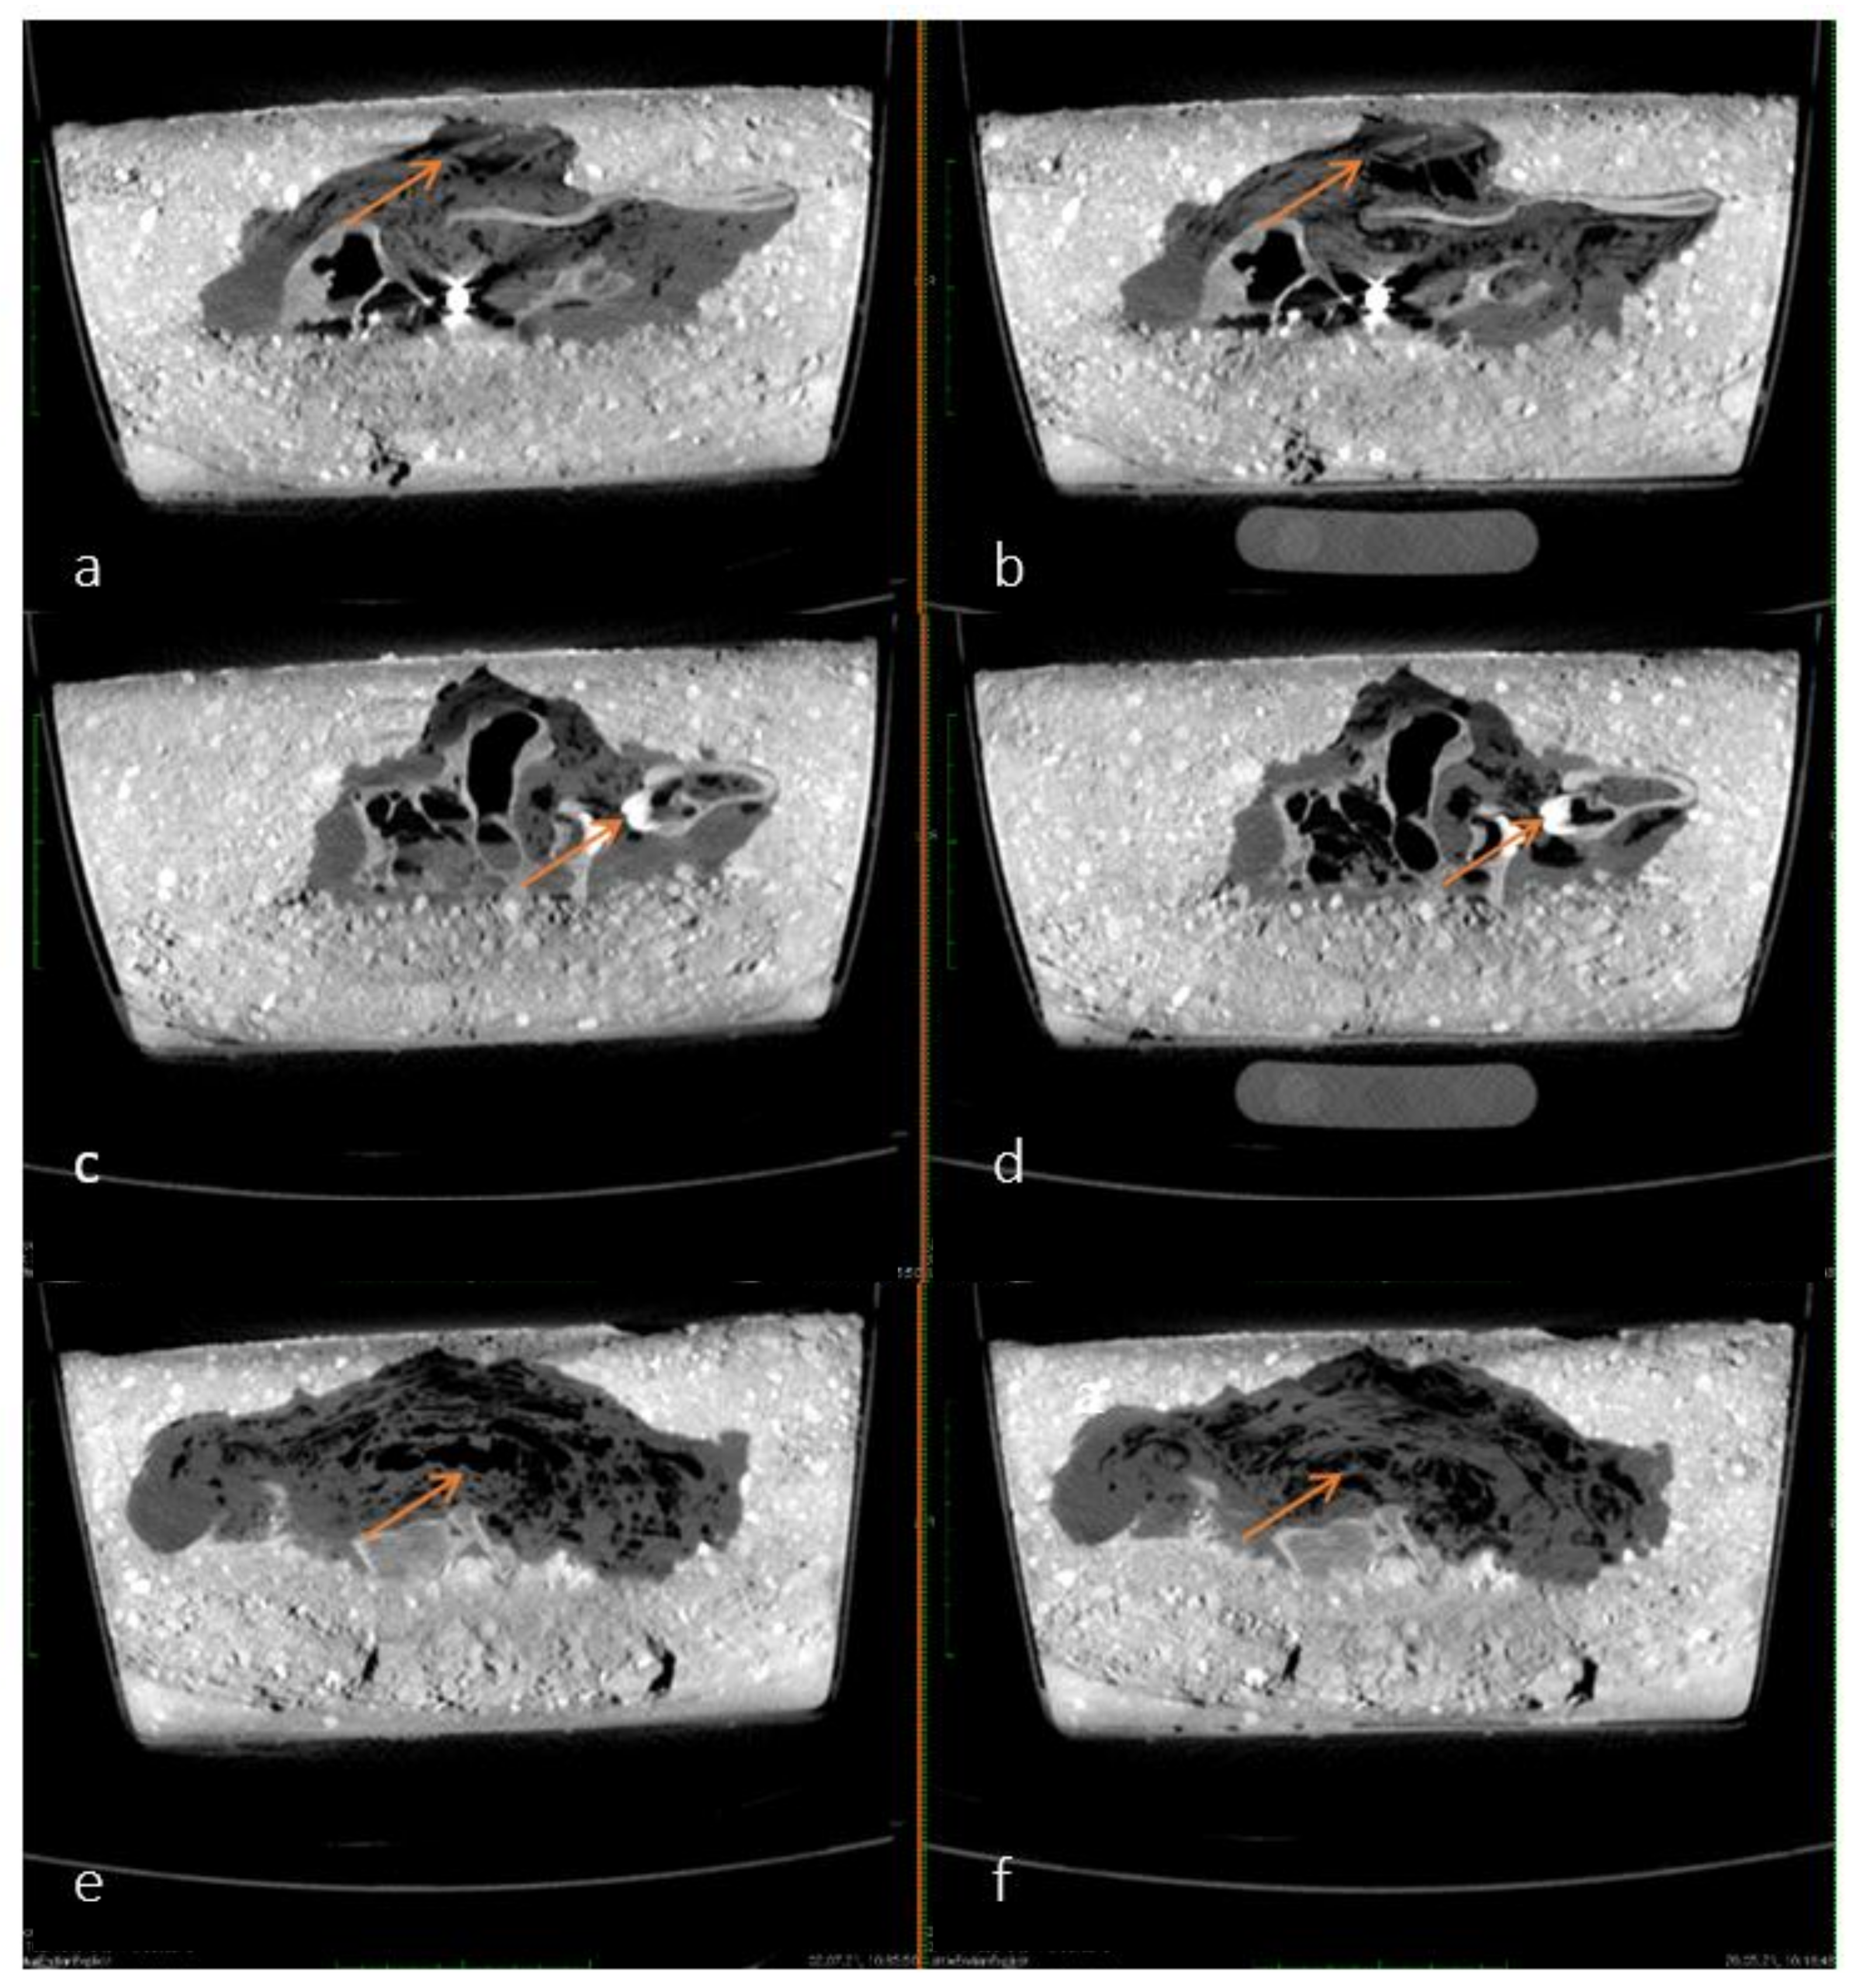

As time progressed, the accumulation and continuous redistribution of air bubbles around the carcass became visible in different slices on the sagittal plane of the pmCT images. The air is exemplified as diffuse black areas marked with arrows in Figure 3a–f. The time interval shown in Figure 3—between 20 May and 2 July 2021, was chosen because the redistribution of air was most visible on these two differential images. These minimal changes occurred continuously in lesser amounts over the course of a year and could therefore not be associated with a specific point in time.

Figure 3.

(a–f) Comparison of pmCT images in sagittal plane from 20 May 2021 (left—a,c,e) and 2 July 2021 (right—b,d,f). Examples of air accumulation and redistribution are shown by arrows.